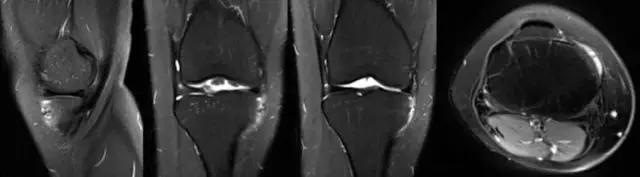

学以致用——

学习不是目的,使用才是目的!阅读MRI后,还应该说给病人听!怎样在病人面前说MRI? 下图为膝关节病损的早期-髌骨软化,MRI显示髌骨出现高信号。 这时应该告知病人:疾病怎么形成?有哪些表现?日常动作有什么影响?怎么治疗?今后病情如何发展?如何保护?

怎样在病人面前说MRI? 髌骨软化进一步发展-髌股关节炎,病情更重,MRI表现更重,股骨滑车也有改变;治疗效果也差。

怎样在病人面前说MRI? 结合解剖、生物力学、影响日常生活的主要症状-上楼梯、爬山疼痛明显,膝关节屈伸有弹响等讲给病人听,直接点到病人的“痛处”。说这些目的应该是为了治疗! 治疗-保守:理疗、关节内注射…… 手术:关节镜、人工关节……